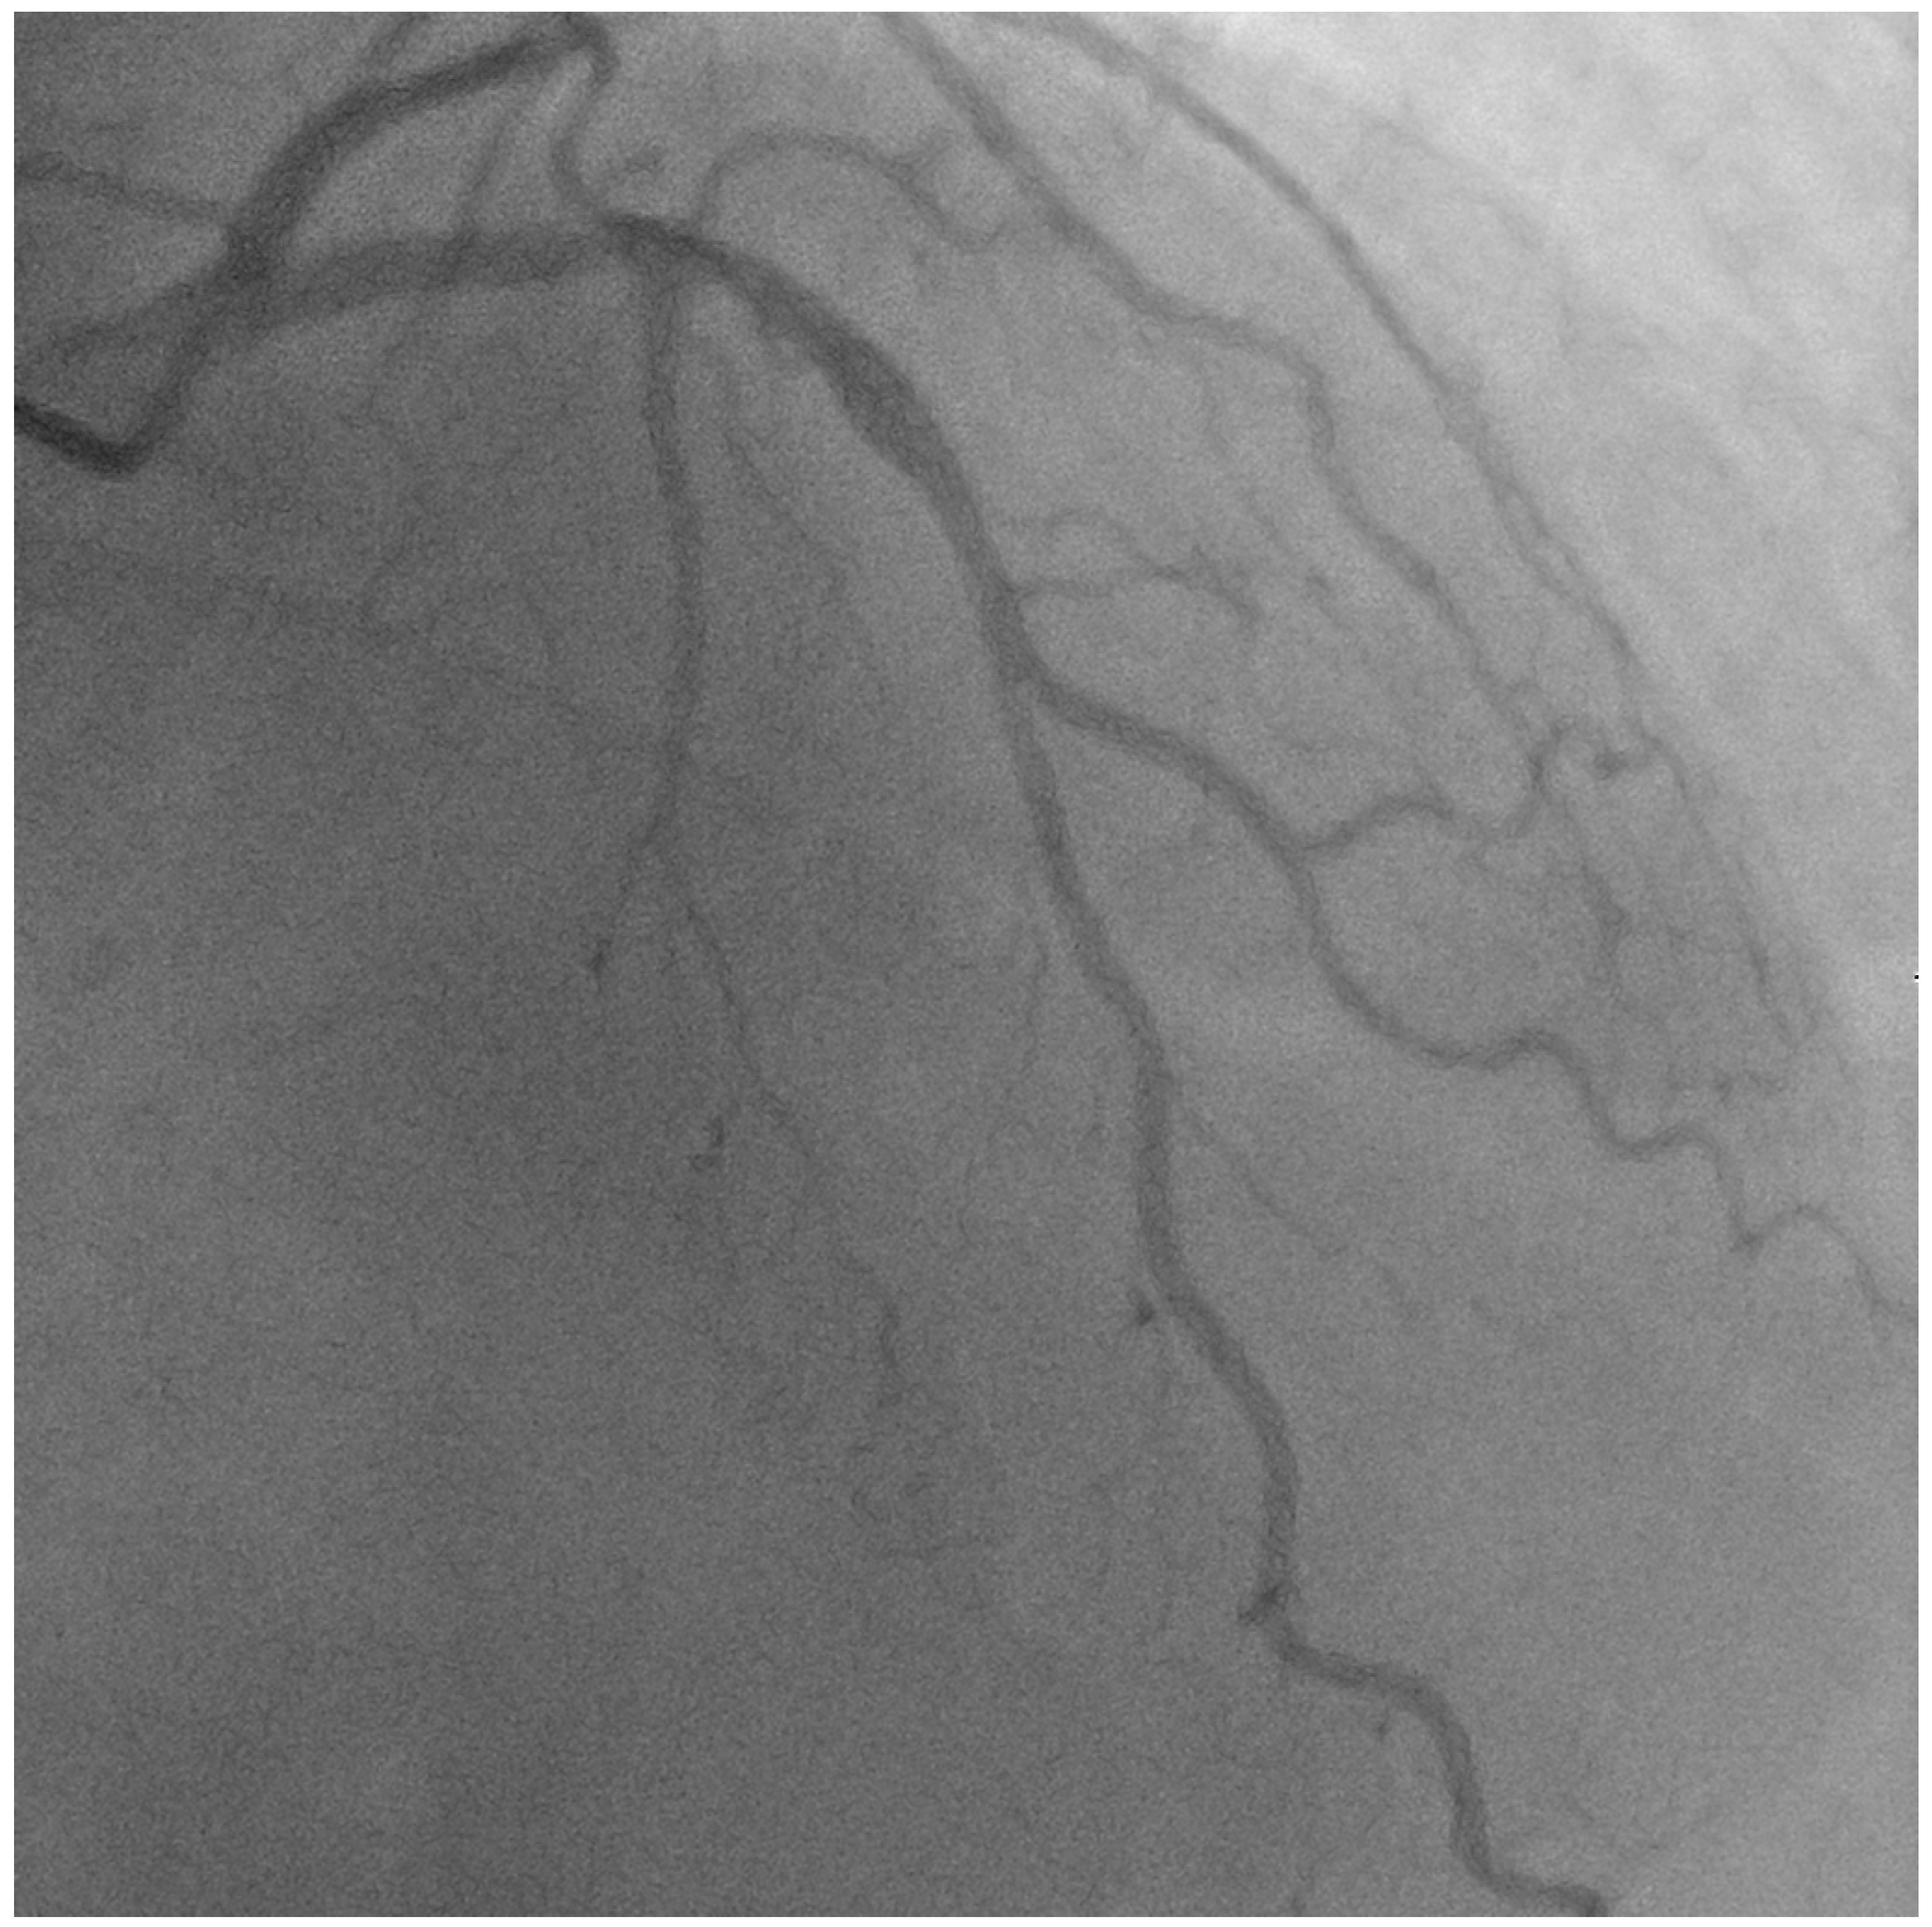

The patient presented again 9 years later with in-stent restenosis (ISR) of the mid-LAD and required a repeat PCI using a 2.5 × 28 Xience Aline stent. The patient continued to come back with recurrent ISR over the next follow-up years until he passed away, 11 years after the index procedure. A coronary angiogram performed 11 years later showed a patent diagonal artery without any obstructive ostial disease (Figure 9).

Figure 9.

Coronary angiogram recorded 4 years post-PCI, showing a stable LAD/diagonal bifurcation (A). Coronary angiogram recorded 6 years post-PCI, showing a stable LAD/diagonal bifurcation (B). Coronary angiogram recorded 9 years after the initial PCI, showing the mid-LAD in-stent restenosis (C).